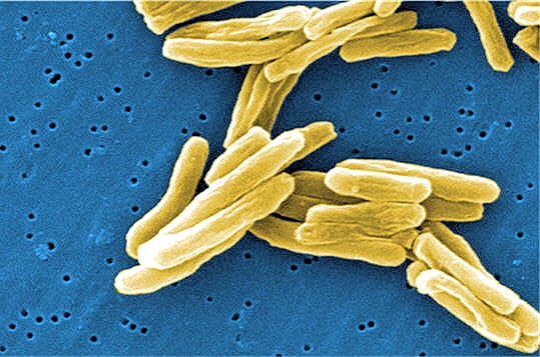

Infection tuberculeuse pulmonaire

La tuberculose est une maladie provoquée par une bactérie nommée Mycobacterium tuberculosis ou aussi bacille de Koch découverte par un médecin allemand Mr Koch en 1882. Cette bactérie évolue dans le milieu aérien et est donc transmise majoritairement par voie aérienne, même si elle se transmet aussi par voie orale ou digestive. Ainsi, une personne infectée peut transmettre le bacille par la toux, l’éternuement ou encore par le simple fait de parler. Il existe trois types de tuberculose : la tuberculose pulmonaire, étant la plus répandue puis la tuberculose extrapulmonaire qui intervient lorsque les bactéries attaquent des parties du corps autres que les poumons telles que les os. Le dernier genre de tuberculose est la tuberculose disséminée qui attaque le corps entier car les bactéries se répandent par le système sanguin. La tuberculose pulmonaire intervient dans 70 % des cas, dans ce cas les bactéries se logent dans des gouttelettes en suspension et, lorsqu’elles sont ingérées, infectent les poumons. A ce stade, l’infection peut devenir soit active soit devenir une infection tuberculeuse latente (ITL). Dans le cas de l’ITL, la bactérie est vivante mais inactive ainsi le sujet ne présente aucun symptôme cependant elle peut se transformer en infection active au cours du temps. Dans le cas d’une infection active la bactérie détruit petit à petit les poumons et le sujet présente alors les symptômes de la maladie.

Le bacille de Koch